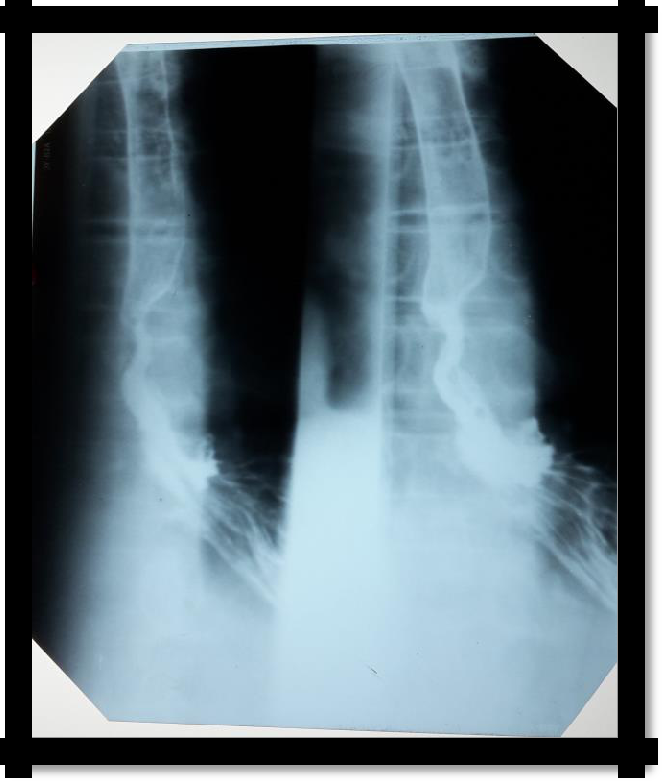

Pic 4.1 Organic esophageal stenosis